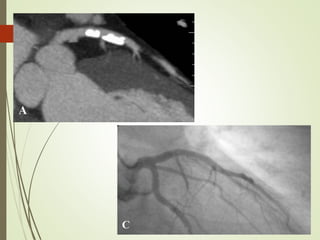

Two large, predominantly non calcified plaques in proximal RCA

Napkin ring sign with histological evidence of necrotic core and spotty calcification

Two large, predominantlynon calcified plaques in proximal RCA Napkin ring sign with histological evidence of necrotic core and spotty calcification